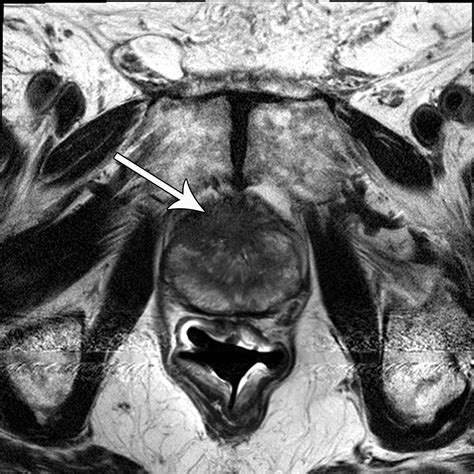

• Multiparametric MRI (mpMRI): This technique combines multiple MRI sequences, including T2-weighted imaging, diffusion-weighted imaging (DWI), and dynamic contrast-enhanced (DCE) imaging, to provide a comprehensive evaluation of the prostate.

• Prostate Imaging Reporting and Data System (PI-RADS): This standardized reporting system helps radiologists interpret MRI findings and classify the likelihood of clinically significant prostate cancer.